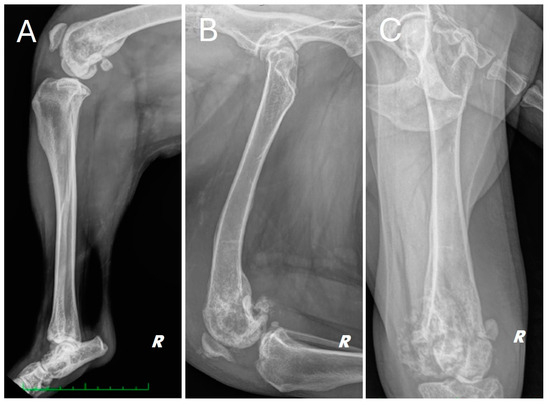

A total body computed tomography (CT) study using a 16-slice helical scanner (Somatom Emotion 16; Siemens, Erlangen, Germany) was performed to determine the extent of the neoplasm and its borders, the degree of cortical proliferation and soft tissue infiltration and the presence of any pulmonary metastases that were not visible on conventional radiography. The patient was sedated with a combination of intravenous dexmedetomidine (Dexdomitor, Vétoquinol Italia S.r.l., Bertinoro, Italy; 0.005 mg/kg) and butorphanol (Dolorex, MSD Animal Health S.r.l, Milan, Italy; 0.3 mg/kg) and then positioned in sternal recumbency with both thoracic limbs extended cranially and both pelvic limbs extended caudally. The CT acquisition parameters were 120 kVp and 150 mAs. A helical total body scan was reconstructed in a pre- and post-contrast 1 mm standard algorithm, and a 0.6 mm scan from the ilium to the toes was reconstructed using the bone algorithm. Contrast was administered IV at a dose of 770 mg iodine/kg of non-ionic contrast (Omnipaque, 350 mg iodine/mL, GE Healthcare Inc., Marlborough, MA, USA). After the acquisition of the planning CT study, the surgeon evaluated the tumor with a radiologist. The examination confirmed the presence of an aggressive lesion localized to the right distal femur, characterized by marked bone lysis, pronounced periosteal reaction and extensive increase in intramedullary density extending into the middle third of the diaphysis of the femur (Figure 2).

In addition, CT showed a complete comminuted and slightly dislocated fracture of the medial femoral condyle ipsilateral to the injury, with marked swelling of the joint and periarticular soft tissues extending to the course of the long digital extensor, hypomyotrophy of the right limb with mild lymphadenomegaly of the medial iliac and sacral lymph nodes on the same side. Multifocal osteoarthrosis involving the elbow, tarsi and coxofemoral joints with mild bony remodeling, smooth margins and mild joint tumefaction were also noted. The CT scan showed no evidence of pulmonary metastases.

Figure 2. (A) CT scan of the right distal femur. (B) CT scan of the knee joint; pathologic fracture of the medial femoral condyle (orange arrowhead) joint effusion (blue arrowhead).